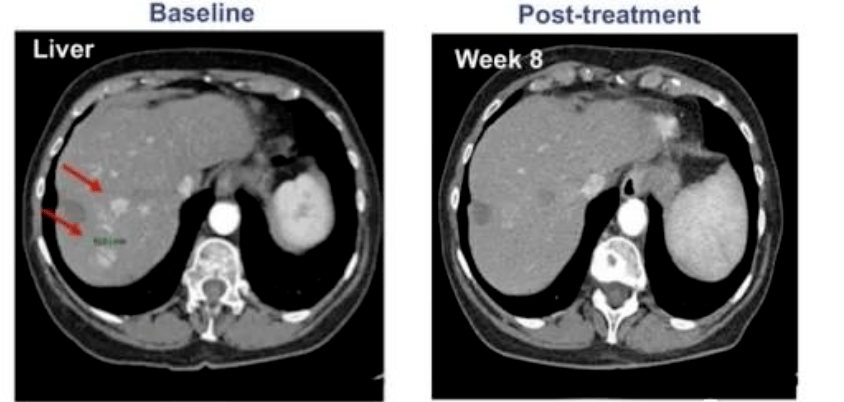

所有 9 名患者均接受了手術、常規放療和化療,但出現了失敗或不耐受。在接受最高劑量治療的 4 名患者中,有 1 名患者病情完全緩解。CT 掃描顯示,患者體內所有病變均已消失,完全緩解后半年多沒有復發!